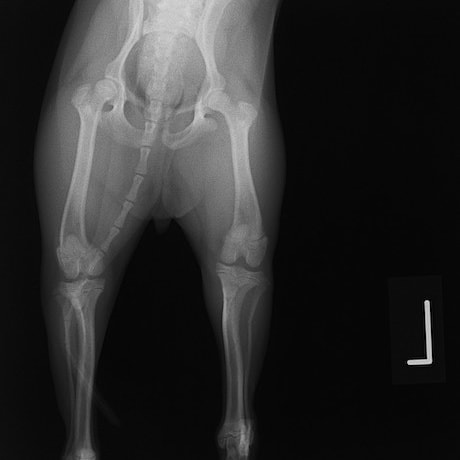

ペルシャ猫 11ヶ月齢 雄

他院にて左大腿骨遠位の成長板骨折(salter-harrisⅠ型)が認められており、治療相談を目的として来院。当院にて、キルシュナーワイヤーを用いたピンニングにより骨折部位の整復を行いました。術後の経過は良好で、現在も経過観察中です。

術前レントゲン